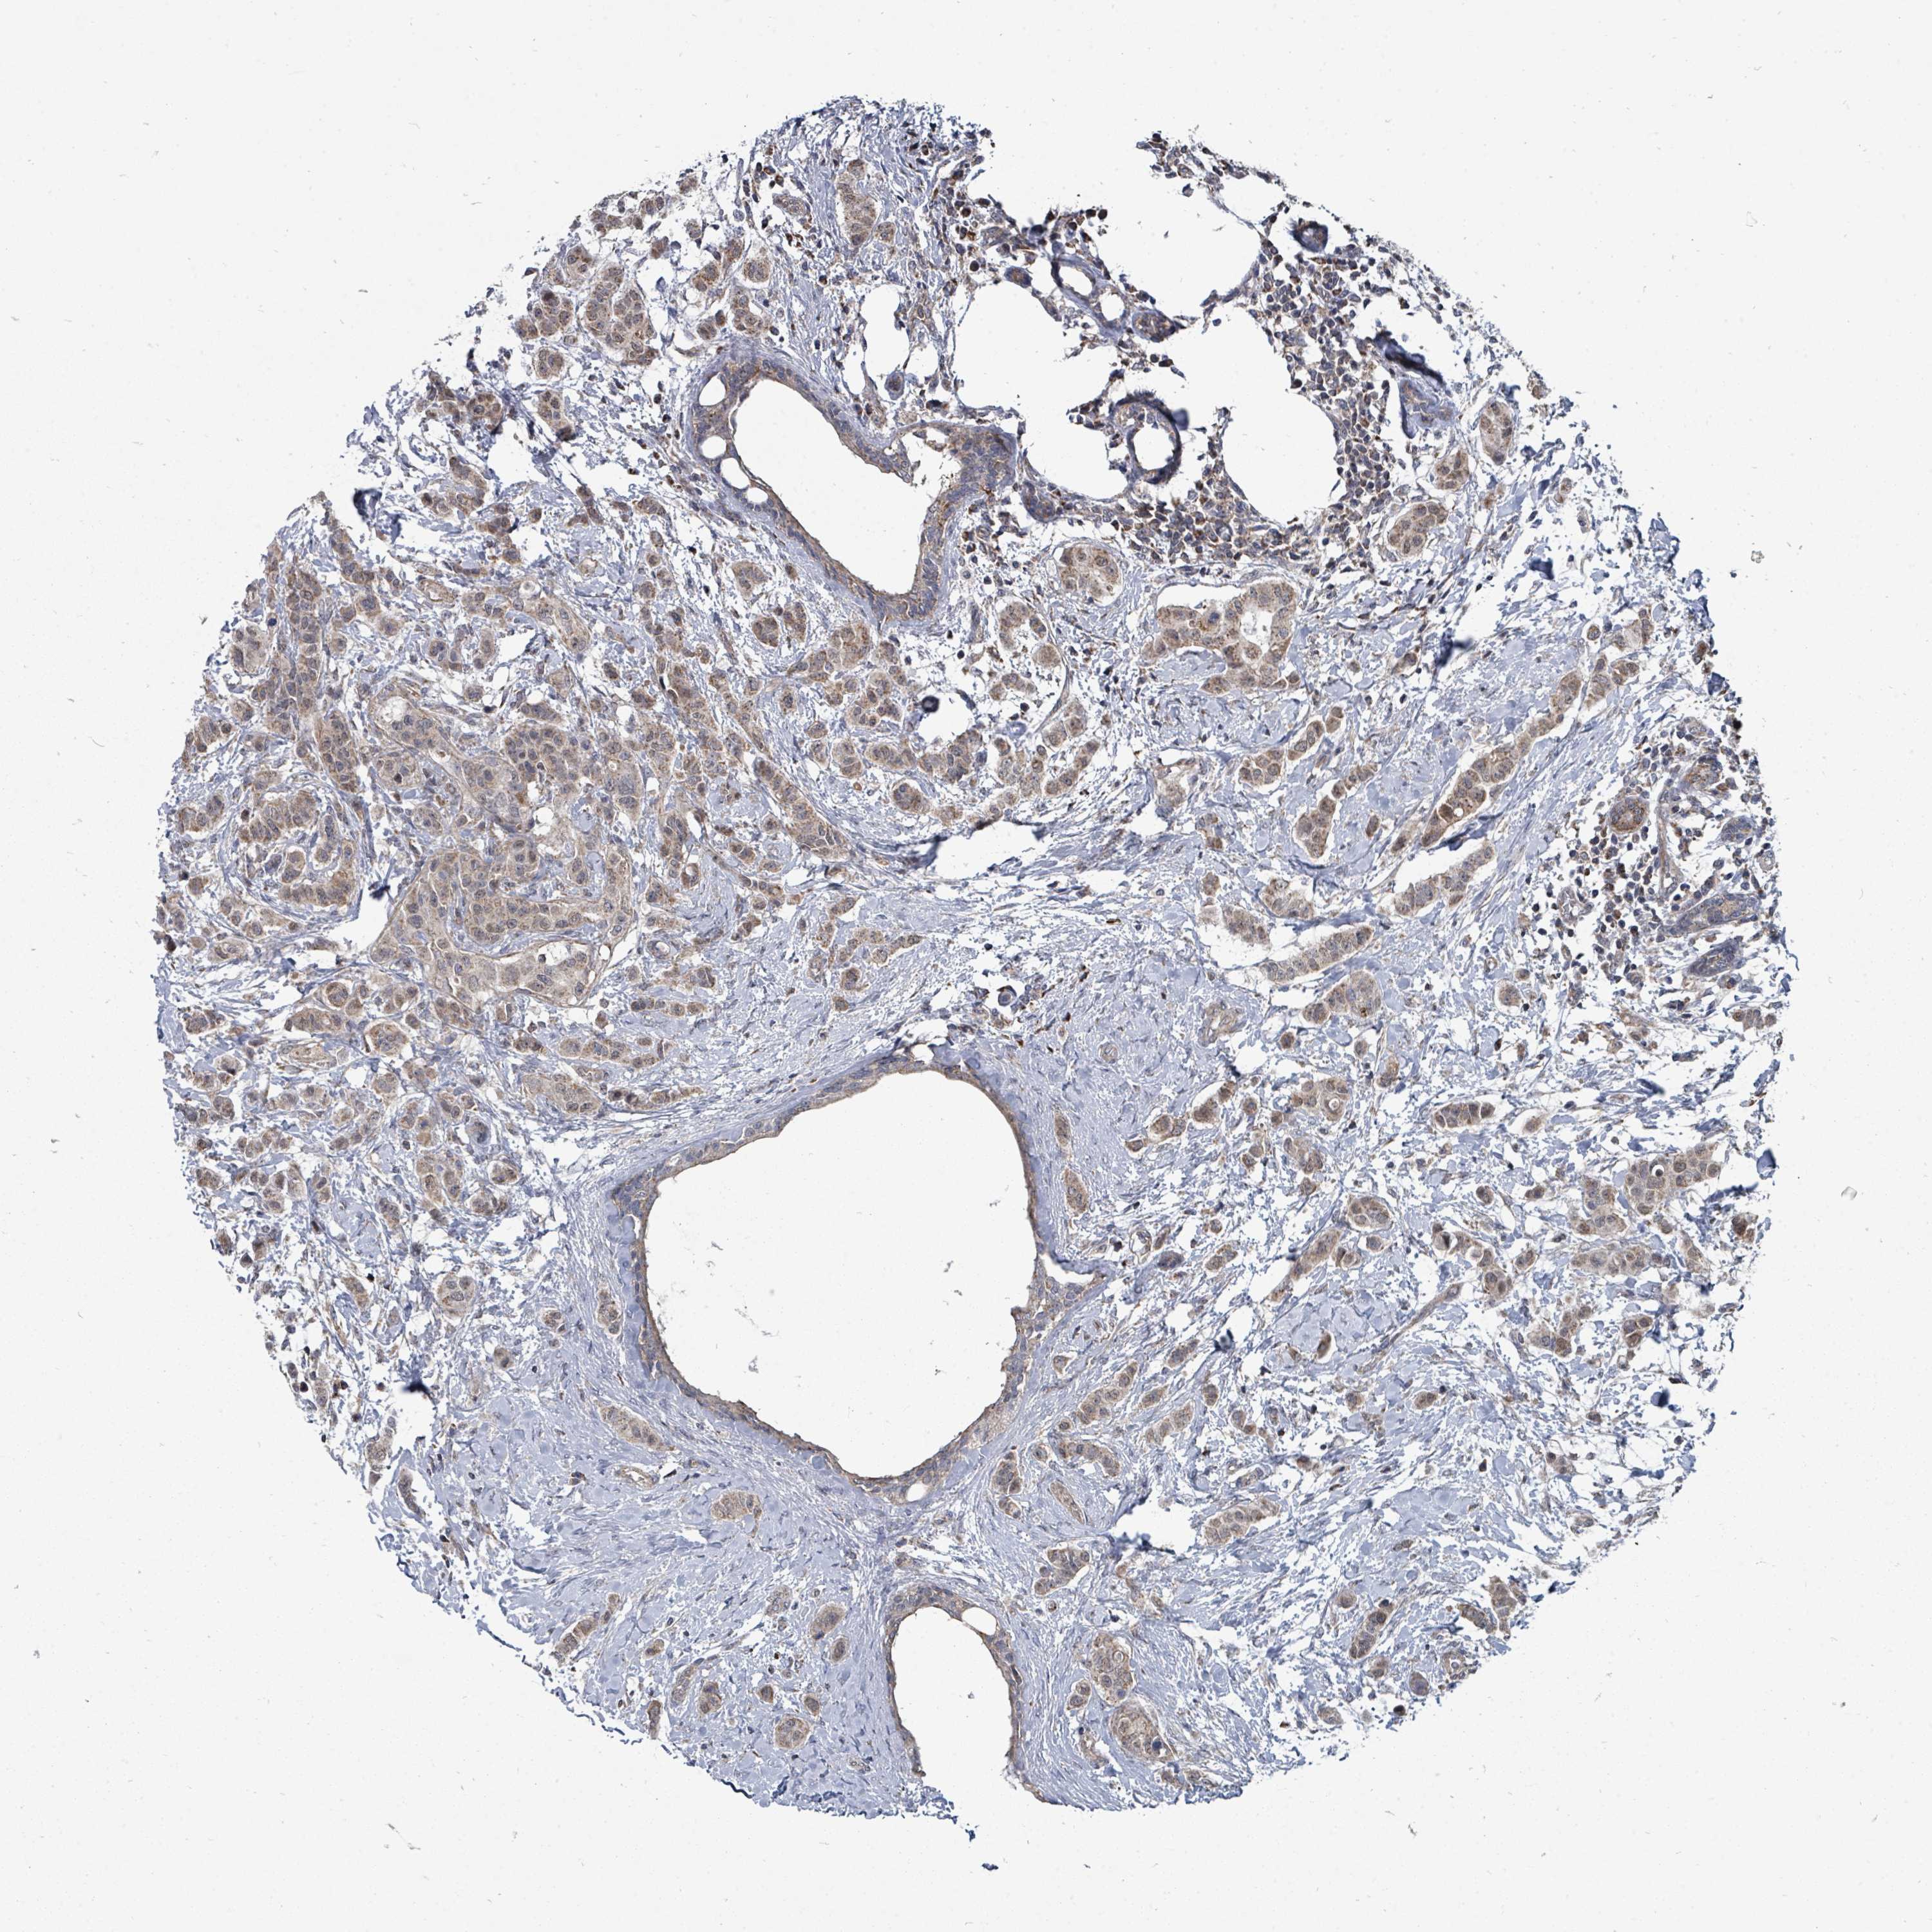

CANCER BREAST CANCER Show tissue menu

BRCA TCGA BRCA VALIDATION PROTEIN EXPRESSION